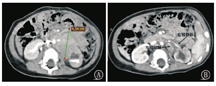

11例患儿术前均行CT检查(图1A、图1B)并完成三维重建,并分色打印出3D肿瘤模型,动脉红色,下腔静脉系统血管蓝色,门静脉系统血管绿色,肿瘤部分用红褐色表示(图2、图3)。应用3D打印模型交代病情后患儿家长对肿瘤大小与位置、与周围血管关系、手术方式及并发症等的知晓率较CT沟通病情显著提高(表2),相关问题知晓率升高至:肿瘤大小与位置100%(11/11例)、与周围血管关系90.9%(10/11例)、手术方式81.8%(9/11例)、手术并发症90.9%(10/11例)。